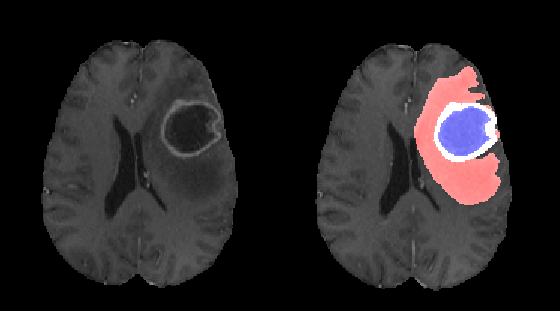

Brain gliomas can be well detected using magnetic resonance imaging. The whole tumor is visible in T2-FLAIR, the tumor core is visible in T2 and the enhancing tumor structures as well as the necrotic parts can be visualized using contrast enhanced T1 scans. An example is illustrated in figure 1.

Due to our training data preparation (class wise segmentation smoothing) and due to our data augmentation method (additive noise), our segmentation results tends to be smoother than the ground truth segmentation. This effect is illustrated in figure 6.

Different segmentation results are illustrated in figure 7. The proposed network tends to produce smooth and compact segmentation results which are often very close in terms of Euclidean distance to the ground truth segmentation. We have consciously chosen to privilege this effect by smoothing the ground truth segmentation and augmenting data with additive noise. Different approaches may be better suited for other kind of quality metrics.